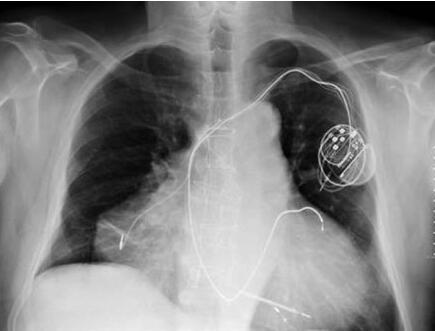

2010年,起初这个病人并没有任何特殊的异常,他呼吸急促伴有血压偏低,毫无疑问这是心血管问题。急诊室的医生经常看到这种类似的症状。

医生们认为他患有典型的心脏骤停,直到他们做了更加细致的检查后才注意到他不同寻常的疾病。事实证明,这个男人并不是先天具有两个心脏,第二个心脏是在他进行早期医疗的时候出现在原心脏上的。

采用心脏异位移植会出现一对新的心脏,一个正常的和一个病变的。这当然也有内在风险,因为移植成功的话会出现两个独立的心律,但在这种情况下,一个心脏会更好一点。进了医院以后,医生对他进行了药物治疗,试图纠正他的节律障碍,并使用药物方法使他的两颗心脏停工,之后再用电击器使两颗心脏同时恢复功能。据报道,目前男子的两颗心脏都运作正常。